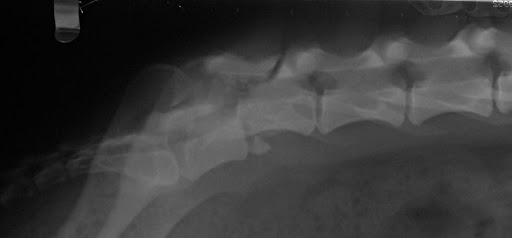

Σκύλος προσκομίστηκε στο Κτηνιατρικό Κέντρο Ιλισίων μετά από τροχαίο ατύχημα. Διαπιστώθηκαν εξάρθρημα ισχίου, κάταγμα ηβοισχιακής σύμφυσης, εξάρθρημα μεταξύ έκτου καί έβδομου οσφυϊκών σπονδύλων καί κατάγματα ακανθώδους απόφυσης καί κάτω οπίσθιας γωνίας σώματος έκτου οσφυϊκού σπονδύλου. Λίγες ημέρες μετά το ατύχημα εμφανίστηκαν αταξία καί απώλεια των αντανακλαστικών θέσης των οπισθίων άκρων καθώς και αδυναμία κίνησης της ουράς. Παρακάτω φαίνονται οι ακτινογραφίες του εξαρθρωμένου ισχίου πρίν και μετά την κλειστή ανάταξη, οι ακτινογραφίες της σπονδυλικής στήλης πρίν και μετά τη χειρουργική επέμβαση (τροποποιημένη τμηματική νωτιαία σταθεροποίηση) και τα εμφυτεύματα αμέσως μετά την ολοκλήρωση της τοποθέτησής τους και λίγο πριν την έναρξη συρραφής του χειρουργικού τραύματος.